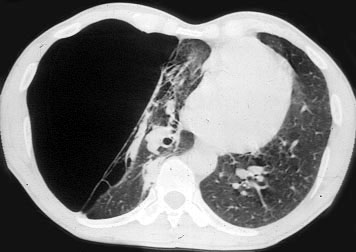

The classification of bullae is useful to evaluate patients as candidates for surgery and to predict the potential functional outcome1,2. One classification scheme is based on the anatomy of the bullae and the quality of the underlying lung:

Group I: Single large bulla with normal underlying lung (Figure 1)

Group II: Multiple bullae with underlying normal lung

Group III: multiple bullae with underlying lung diffusely emphysematous (Figure 2)

Group IV: Multiple bullae with underlying lung affected by other diseases

| Figure 1: Operative view at thoracotomy of a single bulla with normal underlying lung. | Figure 2: Operative view at thoracotomy of multiple bullae with underlying lung with diffuse emphysema. |

Patients in Group I and II are ideal candidates for surgery with predictably good results. Patients in Group III and IV must be carefully selected; functional results and clinical outcome are less predictable, since the quality and functional impairment of the underlying lung is more difficult to evaluate. Bullous disease may also be associated with a complete destruction of the underlying lung and irreversible respiratory failure; in these cases only lung transplantation can be considered if the selection criteria for this procedure are respected.